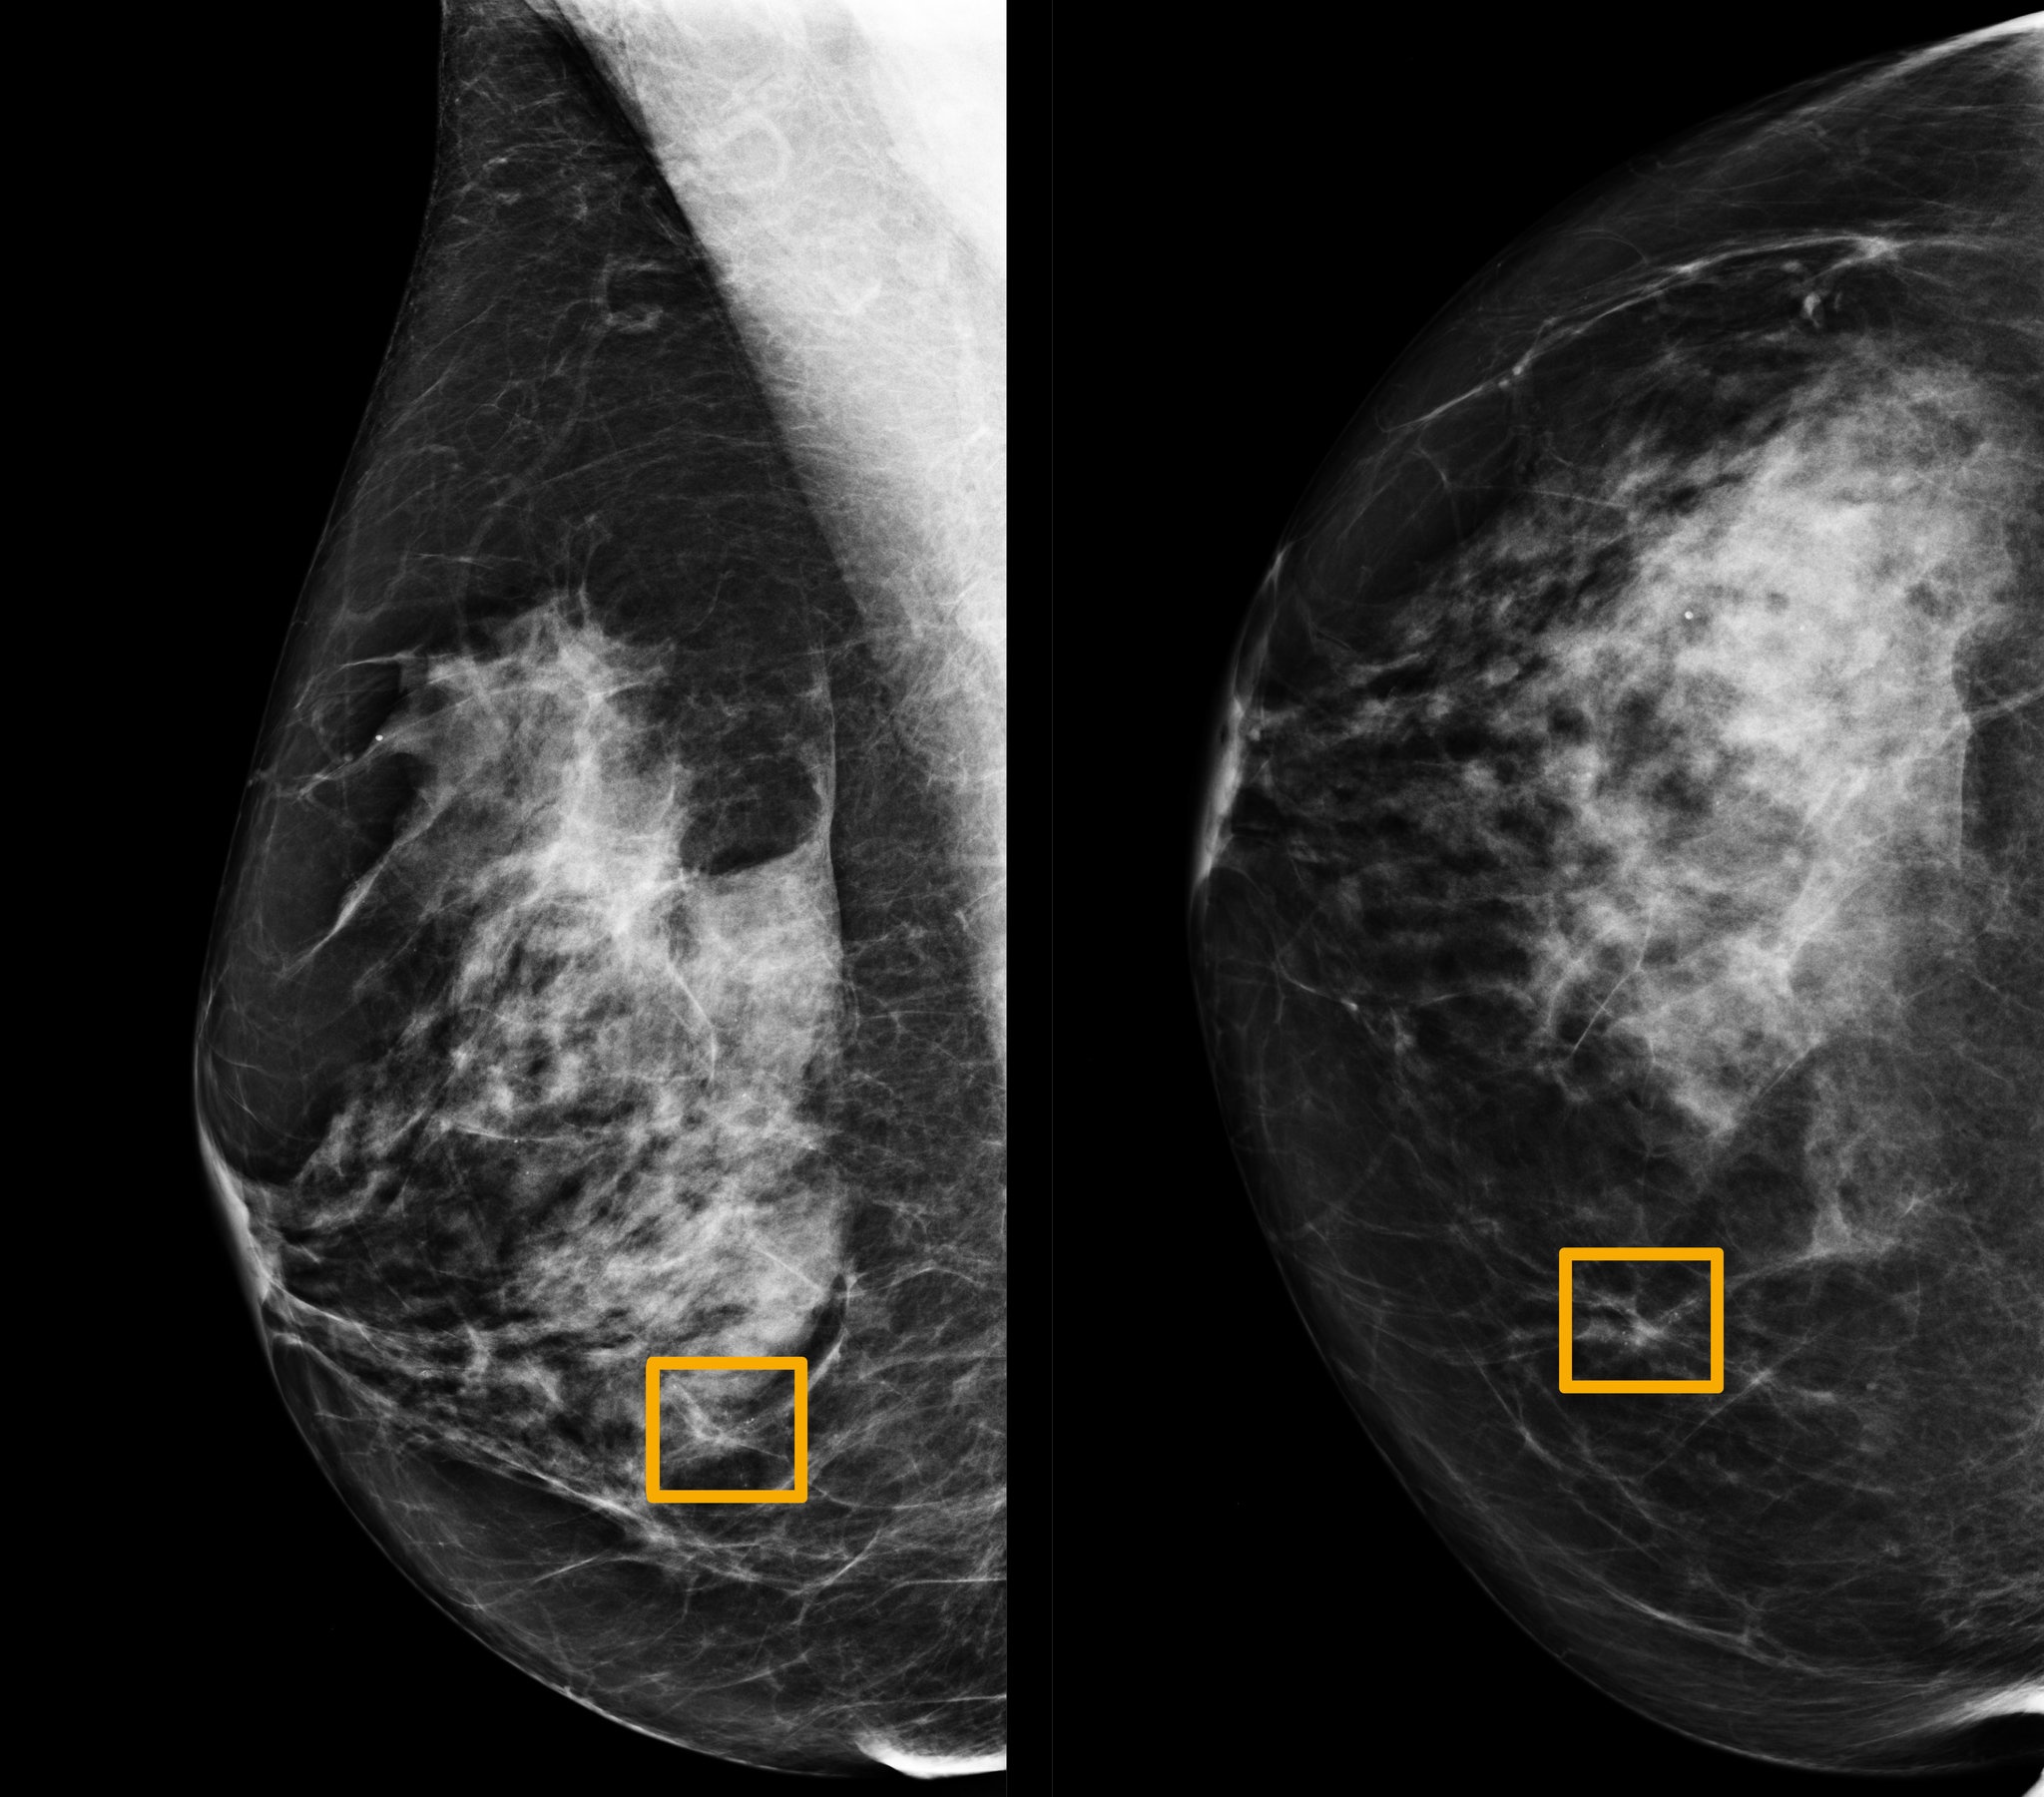

| Ô vàng là nơi mà hệ thống trí tuệ nhân tạo cho rằng có ung thư vú. Ảnh: Đại học Northwestern. |

Kết quả nghiên cứu cho thấy tỷ lệ âm tính giả được giảm xuống 9,4%, trong khi tỷ lệ dương tính giả giảm xuống 5,7% tại Mỹ. Tại Anh, nơi các bác sĩ thường kiểm tra thêm một lần trước khi kết luận, mô hình của Google giảm tỷ lệ âm tính giả 2,7% và dương tính giả 1,2%.